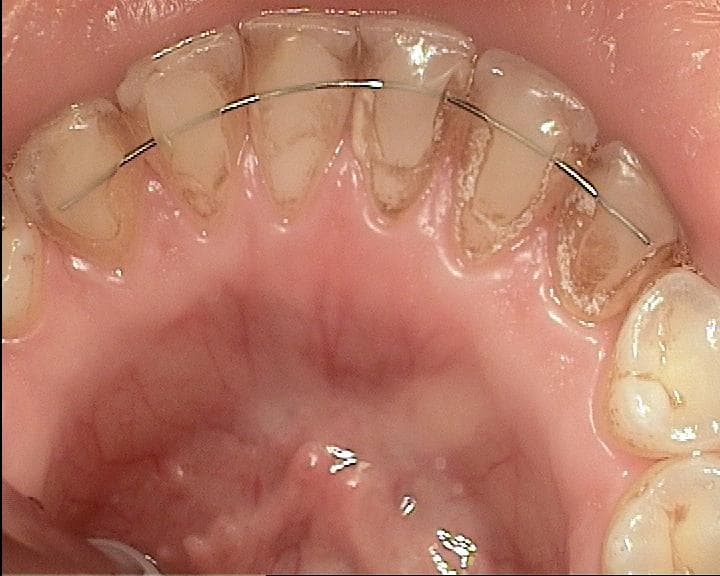

- Panoramik rontgende ilgili alt molar bolge ve yirmi yas disleriyle birlikte genel posterior tablo birlikte okundu.

- Tedavi sonrasi kontrol fotolariyla ikinci yorum secenegi paylasildi.